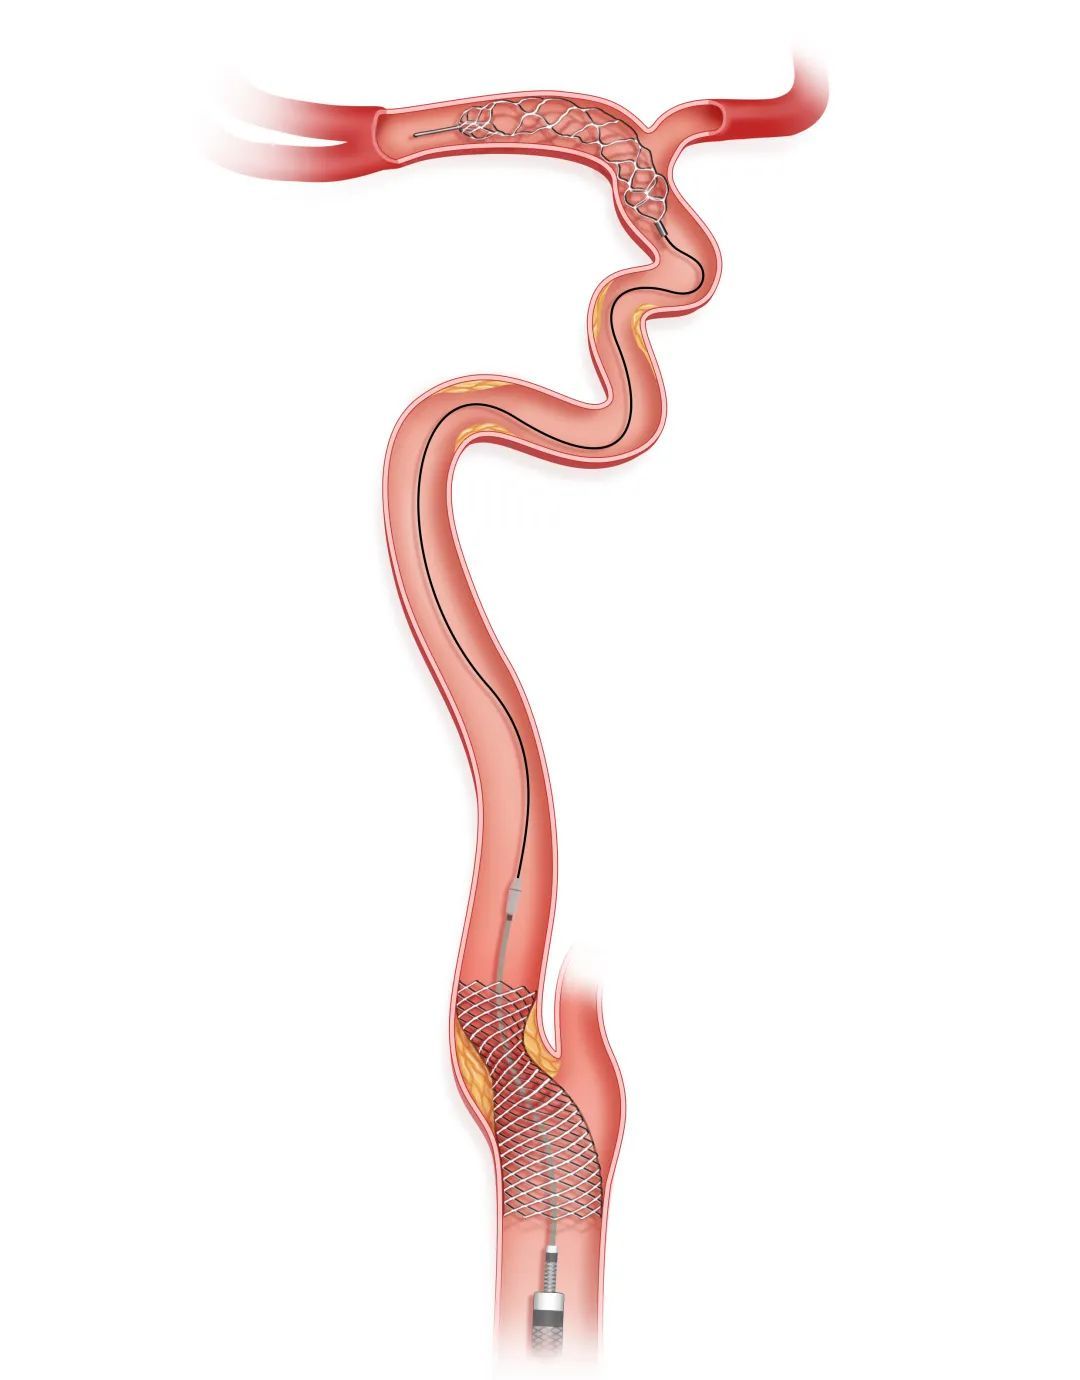

步骤四

Tethys AS®血栓抽吸导管反复抽吸清理血栓

持续负压下前进Tethys AS®血栓抽吸导管,反复抽吸,清理闭塞管腔内的血栓。如果造影发现Syphonet®取栓支架内捕获了脱落的血栓,则回撤Syphonet®取栓支架,清理支架内血栓。